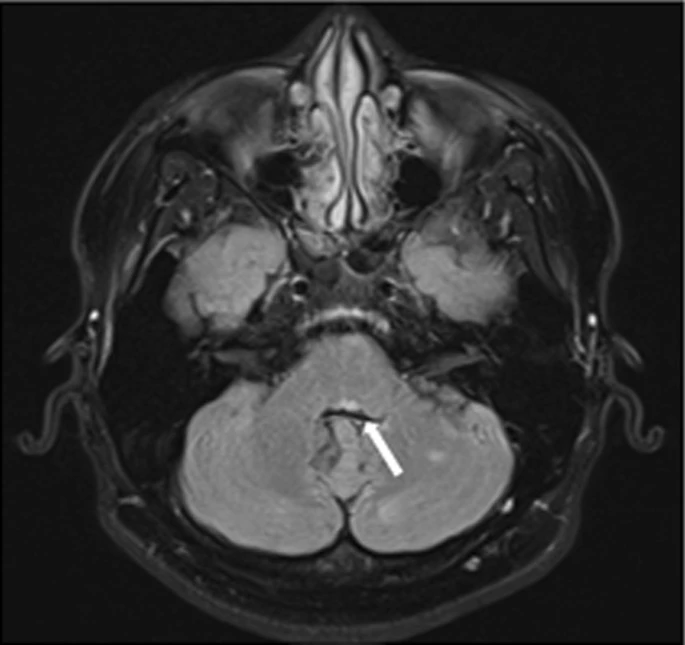

Neuroanatomy Internuclear Ophthalmoplegias Ditki Medical

Internuclear Ophthalmoplegia One And A Half Syndrome YouTube

Internuclear Ophthalmoplegia And One And Half Syndrome YouTube

Internuclear Ophthalmoplegia INO One And Half Eight And Half

Internuclear Ophthalmoplegia INO Plus Syndromes WEBINO One And A